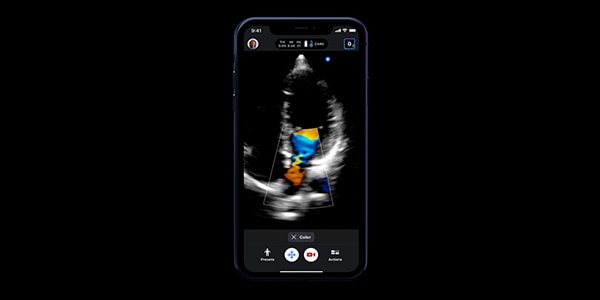

Discover Butterfly iQ+ and how it can make ultrasound easier to use. Plug the probe in your compatible device, select from the available presets in seconds with the swipe of a finger — and start scanning.

• Color Doppler: Color Doppler uses standard ultrasound methods to convert Doppler sounds into colors that are overlaid on the image of the blood vessel. These colors represent the qualitative parameters of haemodynamic behavior and direction of blood flow through the vessel.